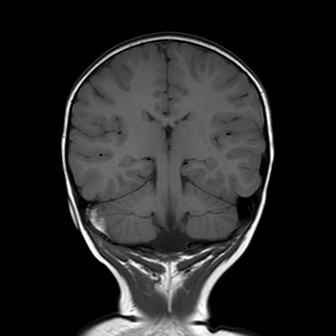

Esegue quindi una TAC che mostra una frattura

dell’osso occipitale con la presenza di un ematoma epidurale

di circa 9 mm adiacente al seno sigmoideo di destra.

La bambina inizia quindi terapia con enoxaparina alla dose di 1700 UI x 2/die con aggiunta di terapia antibiotica con ampicillina-sulbactam per profilassi. Nei giorni successivi Teresa è stata bene, l’instabilità è andata progressivamente scomparendo senza vomito o cefalea. I successivi controlli all’angio-RM e alla TAC hanno mostrato un rallentamento del flusso in seno sigmoideo destro con tumefazione e netta iperdensità dello stesso, che sono andati progressivamente scomparendo con solo una minima falda ematica residua al giorno della dimissione, dieci giorni dopo il trauma. La terapia è stata dimezzata e poi interrotta dopo tre settimane dall’avvio.

La presenza di atassia alla marcia con vomito è un segno tipico della trombosi del seno sigmoideo che, per quanto rara nel bambino dopo un trauma, va esclusa con una angio-RM, non essendo la TAC in grado di visualizzare chiaramente il flusso nei seni venosi, soprattutto se all’immagine si sovrappone la contestuale presenza di un ematoma. Inoltre la progressione dei sintomi neurologici indicava il trattamento del trombo con eparina, a differenza dei casi asintomatici dove è indicata la semplice reidratazione per evitarne la progressione e lo sviluppo di ipertensione endocranica.